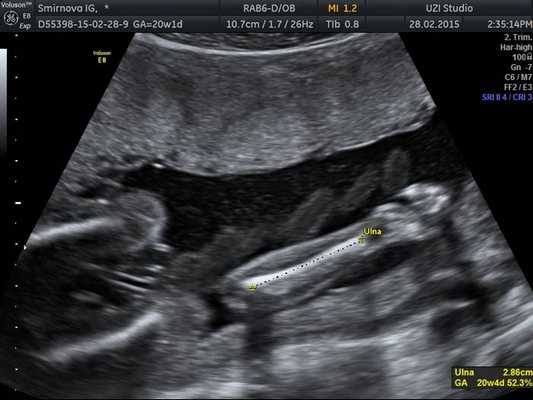

- длина парных трубчатых костей (бедренная, большая и малая берцовая, плечевая, локтевая и лучевая);

Также измеряют длину бедренной кости, плечевой кости, возможно измерение более мелких костей предплечья и голени.